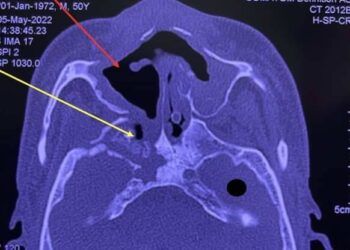

Kết luận về các ca bệnh hoại tử xương sau mắc Covid-19 tại TP HCM có liên quan đến thiểu dưỡng cục bộ của xương sọ - mặt và bội ...

Nhiều bệnh nhân nhập viện trong tình trạng lung lay răng, chảy mủ, sưng đau họng… Kết quả thăm khám cho thấy xương hàm xuất hiện phần hoại tử.

Thời gian qua, một số bệnh viện tại TP HCM như Răng Hàm Mặt Trung ương, Tai Mũi Họng, Chợ Rẫy tiếp nhận nhiều bệnh nhân hoại tử xương sọ, ...

Ngày 13/7, bác sĩ Nguyễn Văn Tuấn, Trưởng Khoa Phẫu thuật hàm mặt, Bệnh viện Răng hàm mặt Trung ương TP HCM, cho biết trong 16 bệnh nhân hoại tử ...